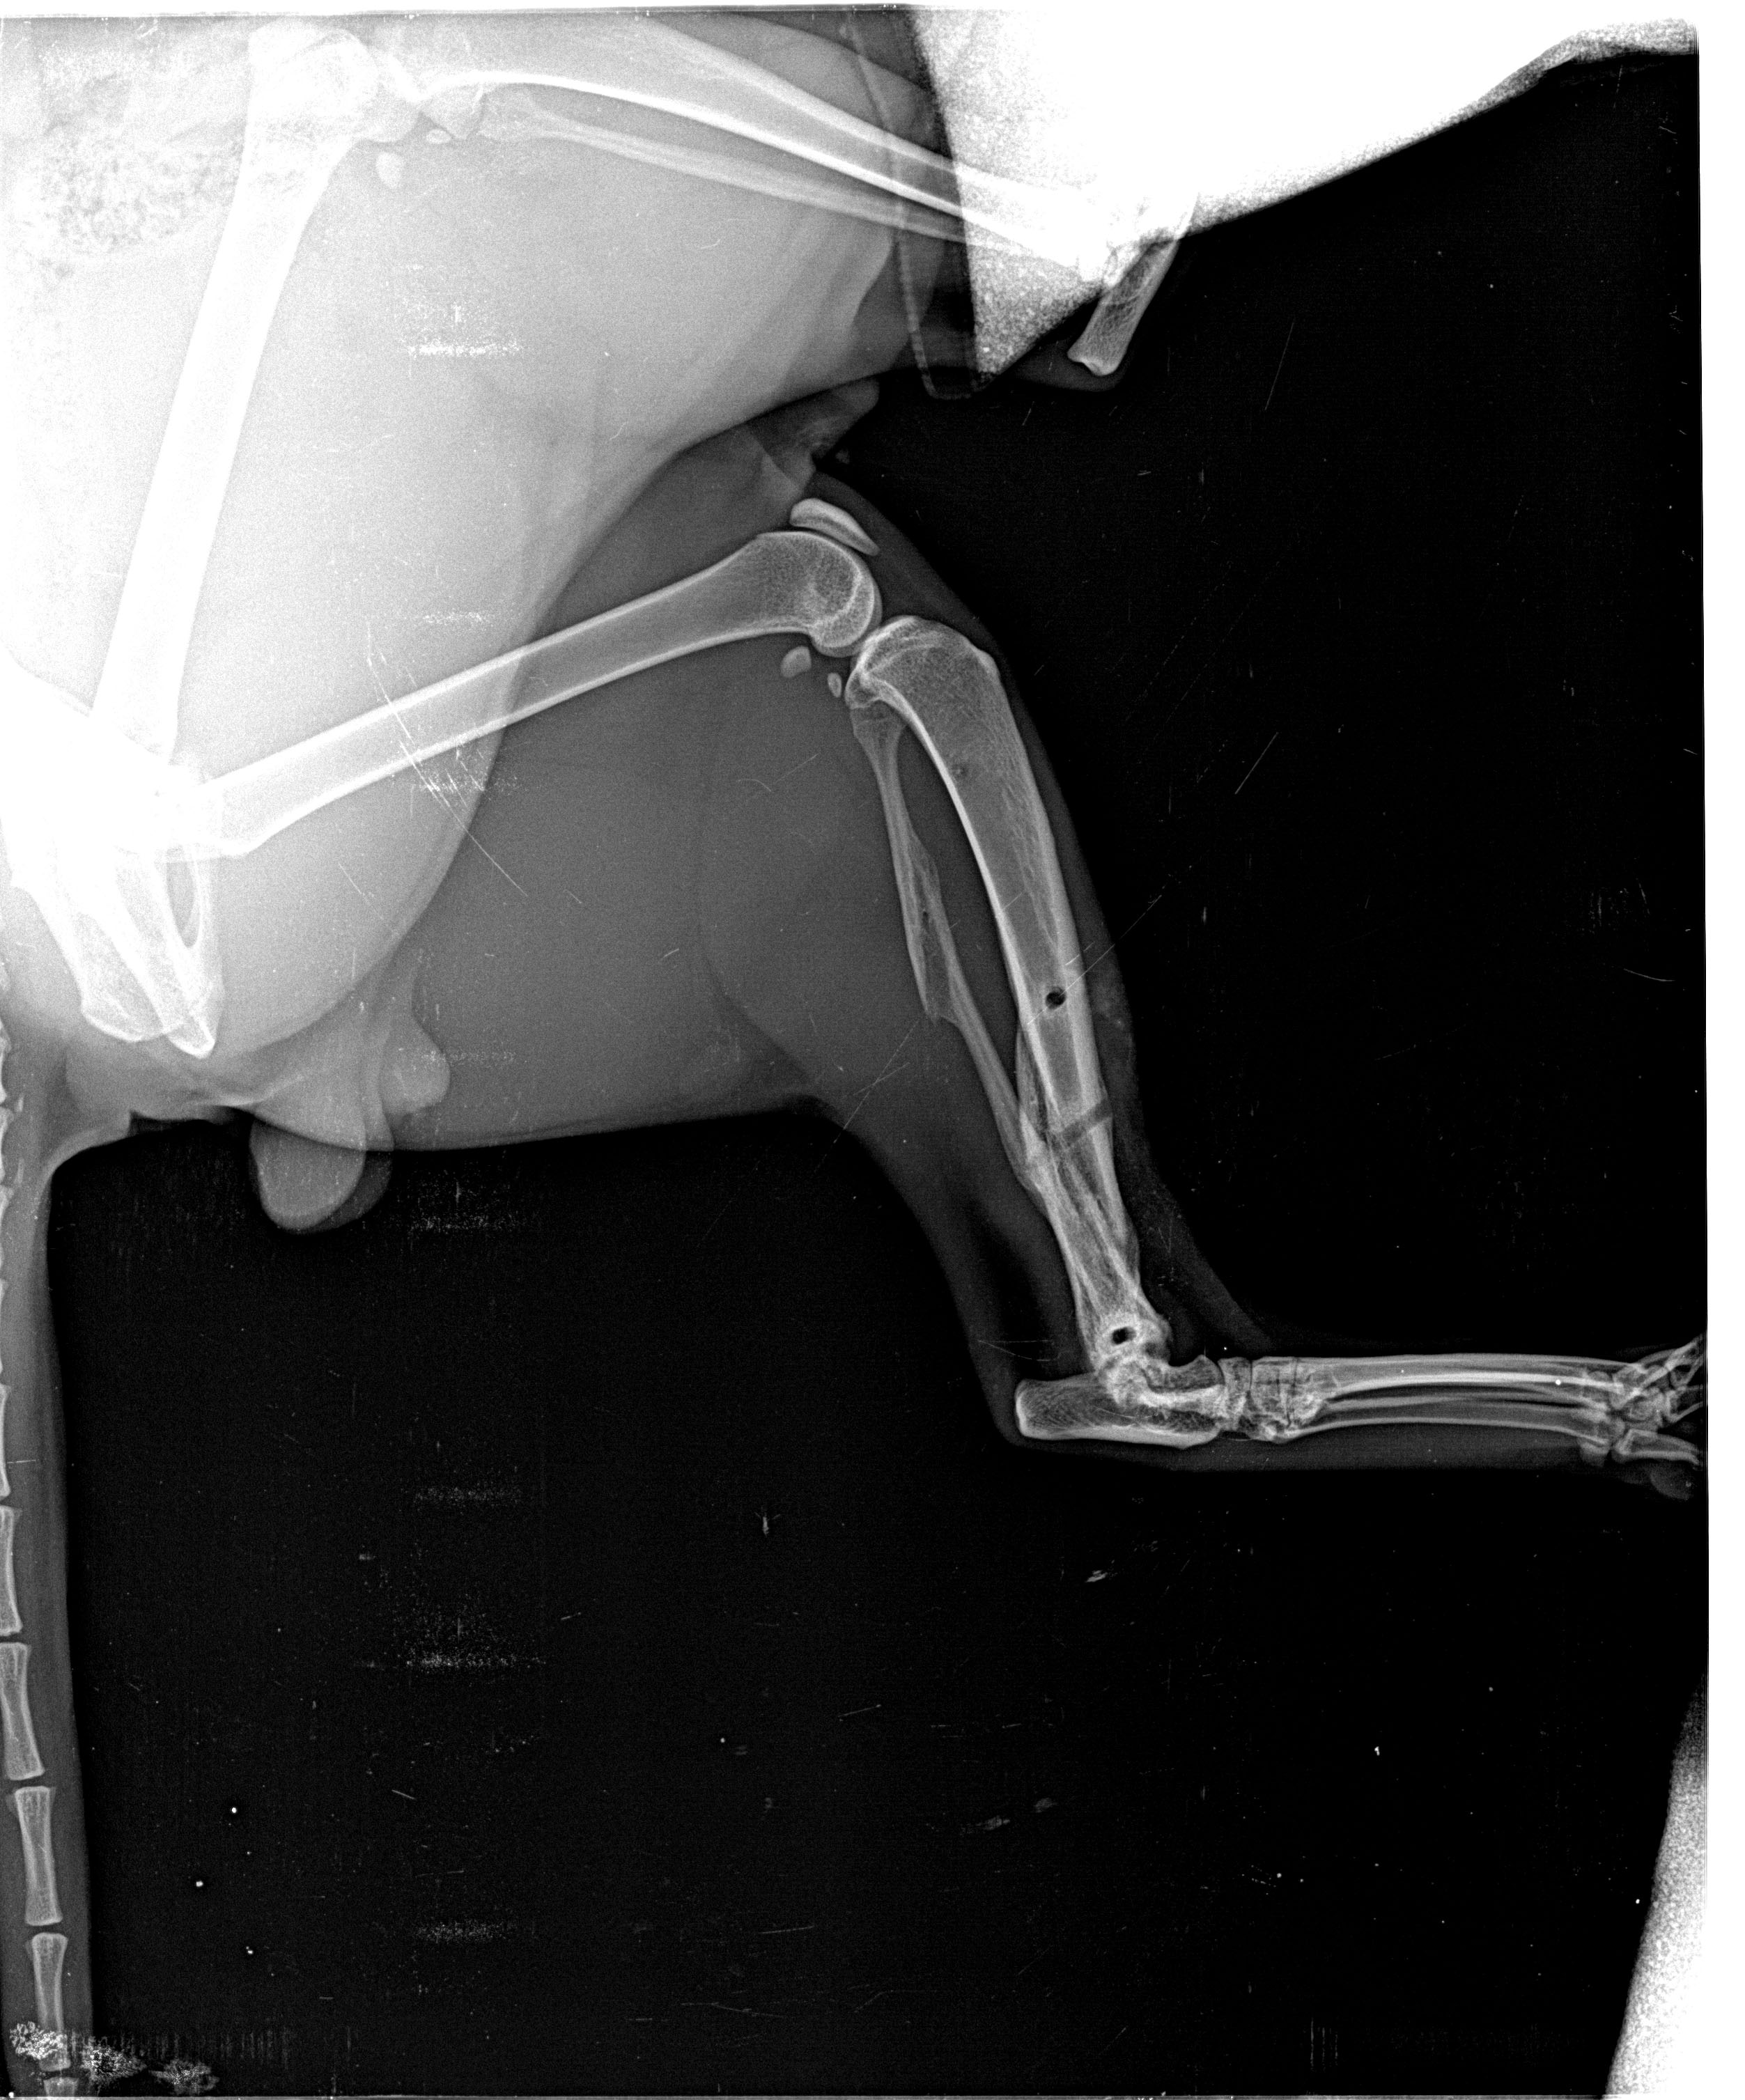

Το εκτόπισμα του Αλέκου, όπως αποδείχτηκε, ήρθε σε σύγκρουση με την κυριαρχική, έως και δεσποτική, προσωπικότητα κάποιου από τη γειτονιά. Και καθώς ο Αλέκος δεν υπολόγιζε την ανθρώπινη δύναμη του κακού, δέχτηκε τις συντριπτικές της συνέπειες στο ποδάρι του... Και μιλάμε για το πίσω πόδι του. Την έφαγε, προφανώς, μπαμπέσικα από χέρι δυνατό και οργισμένο. Συντριπτικό κάταγμα κνήμης και περόνης.

Ο Αλέκος μας, έτσι, πέρασε στα χέρια του Αλέκου Υφαντή. Έγινε στο ποδαράκι του Αλέκου εφαρμογή εξωτερικής συσκευής-μινιατούρας Ilizarov. Τα θραύσματα οστών αφαιρέθηκαν και εισήχθη κάποιο πρωτοποριακό υλικό για οστεογένεση. Τέσσερις ώρες χειρουργείο, με τον Υφαντή να εξέρχεται κάθιδρος κρατώντας στην αγκαλιά του τον ναρκωμένο ακόμα από την αναισθησία Αλέκο. Αλέκος και Αλέκος πέτυχαν το ακατόρθωτο! Ο μεν πρώτος κατάφερε και έδεσε με τα στεφάνια και τις βελόνες του Ilizarov, στη μικροκλίμακα της γάτας, ένα πόδι που, υπό άλλες συνθήκες, θα είχε ακρωτηριαστεί. Ο δε δεύτερος υπέμεινε, Γενάρη μήνα(!), εγκλεισμό σε ένα δωμάτιο και ένα πελώριο για τα δεδομένα του μηχανισμό -σχεδόν μισού κιλού- να είναι καρφωμένος στο πόδι του. Η αποθεραπεία με το μηχανισμό πήρε δυόμιση μήνες, πολύ γρήγορη για τη βαρύτητα του κατάγματος. Το πόδι του Αλέκου αποκαταστάθηκε σχεδόν πλήρως. Ο Αλέκος βγήκε ξανά περήφανος στη γειτονιά και ο εχθρός του, μετά από δυόμιση μήνες εξαφάνισής του, δεν θα πίστευε στα μάτια του.